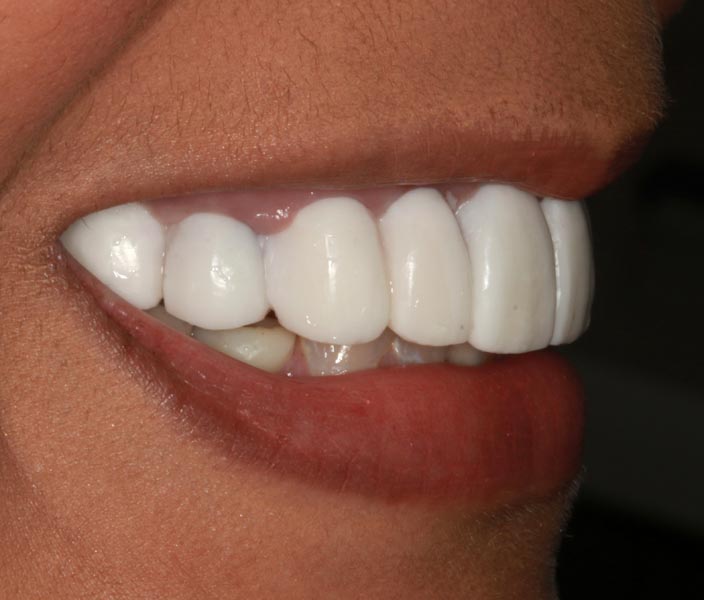

Smile GalleryImplant RestorationsFull Mouth Implant Restoration Full arch zirconia implant bridge (full smile) 1 of 37 Pre-op full smile Pre-op lips retracted Pre-op panoramic x-ray Extraction of strategic teeth Placement of implants Extraction of some remaining teeth after verification of adequate implant stability Occlusal view Post-op panoramic x-ray Immediately fabricated provisional restoration (tissue side view) Immediately fabricated provisional restoration (occlusal side view) Immediate provisional delivered on day of surgery Immediate provisional 2 weeks later Scalloped tissue developed from the provisional at 2 weeks Jig used for making a master impression Provisional in place (full smile) Provisional in place (lips retracted) Provisional in place (right side) Provisional in place (left side) Wax try-in (full smile) Wax try-in (right side full smile) Wax try-in (left side full smile) Wax try-in (full face, lips together) Wax try-in (full smile) Wax try-in (right side) Wax try-in (left side) Wax try-in (lips retracted) Full arch zirconia implant bridge on master cast (frontal view) Full arch zirconia implant bridge on master cast (occlusal view) Implant positions and soft tissue representation on master cast (occlusal view) Soft tissue representation on master cast (frontal view) Full arch zirconia implant bridge (tissue side view) Soft tissues on day of delivery (occlusal view) Soft tissues on day of delivery (frontal view) Full arch zirconia implant bridge delivered (lips retracted) Full arch zirconia implant bridge (lips retracted, close up) Post treatment panoramic x-ray Full arch zirconia implant bridge (full smile)